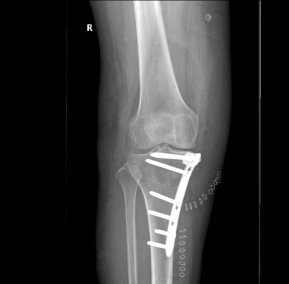

4、力线明显异常的,疼痛和影像学表现在关节局部的,可选择截骨矫正力线,或者膝关节部分置换(单髁置换),这两个手术都尽量保留了膝关节的原始生理结构,效果显著。

此阶段一般需要全膝关节表面置换(TKA),部分患者截骨矫形也有效。